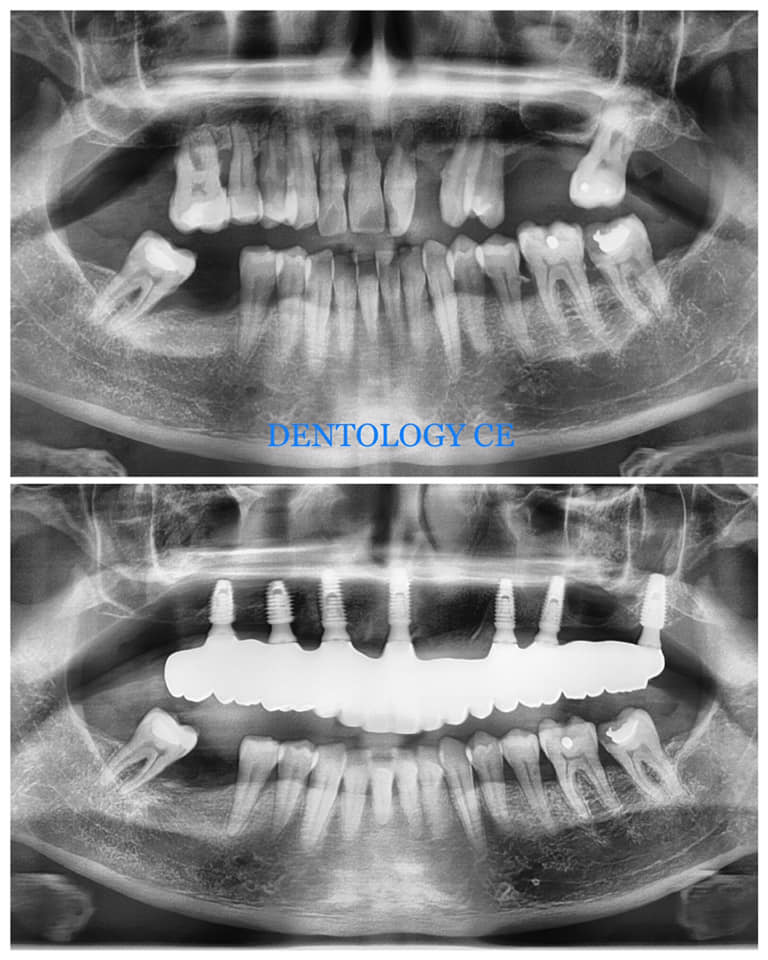

ALL-ON-7 CASE. UPPER, FULL ZIRCONIA BRIDGE.

45y.o male initially presented with failing upper dentition due to chronic advanced periodontitis (gum disease).

After thorough evaluation and diagnosis, which included Cone Beam CT scan, Digital Smile Design – DSD, 3D- intraoral Scanning etc, the treatment plan had been formulated.

All upper teeth had been extracted utilizing special surgical techniques for bone preservation and bone grafting. Among those were: Partial Extraction Therapy (PET), Bilateral Sinus Elevation (Sinus Lift).

Seven dental implants had been inserted using Digital Guided Placement Method. The surgical phase had been finalized with soft tissue grafting to insure proper gum seal around dental implants for long term success and to prevent peri-implantitis.

After completion of bone integration (healing) The final prosthetic phase had been accomplished with fabrication of the full contour zirconia non-removable (fixed) bridge.

ALL-ON-6 BRIDGE CASE

This patient presented with the poor prognosis for his upper teeth, severe bone loss and bite problems.

After thorough evaluation Dr. Andrews recommended ALL-ON-6 fixed implant bridge. The entire surgical stage, including extractions of all remaining upper teeth, bi-lateral sinus lift (right and left side), multiple bone grafts and placement of all 6 dental implants was accomplished by Dr. Andrews in one visit. Six months later the full upper arch dental implant bridge was delivered.